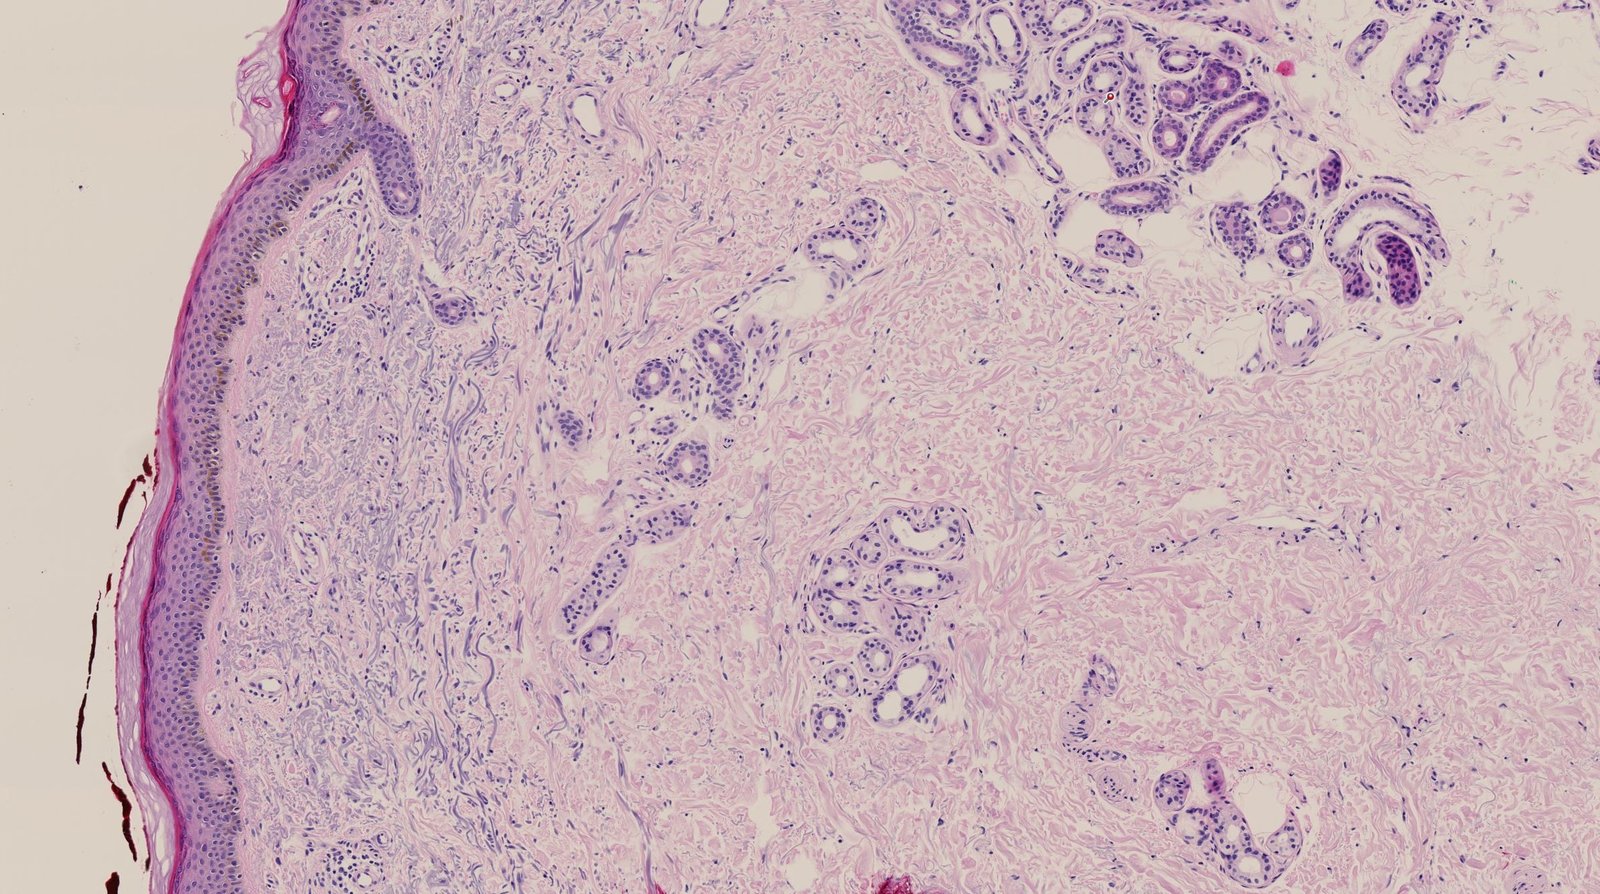

The skin is the largest organ of the body, covering an area of approximately 2 m2. The skin is composed of the cutis (including the dermis and epidermis), subcutaneous tissue, and skin appendages. The epidermis, which is derived from ectoderm, is the outermost layer of the skin and is mainly composed of keratinocytes. The dermis, which is derived from mesoderm, is located underneath the epidermis and is mainly composed of elastic fibers, type I collagen, and connective tissue. It is formed by the papillary dermis and the reticular dermis. The subcutaneous tissue, which is derived from the mesoderm, is the innermost layer of the skin and is mainly composed of fat and connective tissue. Skin appendages are derived from the skin and include hair, nails, and glands. The main functions of the skin are protection (barrier against ultraviolet radiation, microorganisms, and water loss), the synthesis of vitamin D, detection of sensation (e.g., touch, temperature, pain), and the regulation of body temperature.

The skin is composed of several layers, which are categorized as follows (from superficial to deep):

Cutis

Epidermis

Dermis

Derived from mesoderm; contains blood vessels and provides structural integrity to the skin

• Papillary dermis

• Consists of fine, loosely arranged collagen fibers

• Supplies the epidermis with nutrients

• Plays an important role in temperature regulation

• Forms dermal ridges, which connect dermal papillae (extension of the papillary dermis into the epidermis) to epidermal downgrowths known as epidermal ridges or rete ridges

• Contains Meissner corpuscles (for fine-touch and two-point discrimination) and free nerve endings

• Contains immune cells (mast cells and macrophages)

• Reticular dermis

• Consists of thick, densely packed fibers (e.g., reticular, elastic, and collagenous) that provide structure and support to the skin and its components

• Contains Ruffini corpuscles (mechanoreceptors): responsible for mechanical pressure and the sensation of distortion

• Contains sweat glands, sebaceous glands, and the roots of hair follicles

Subcutis (also called hypodermis)

• Derived from mesoderm

• Consists mainly of subcutaneous fat that protects from cold and trauma

• Contains superficial veins and free nerve endings

• Contains Pacinian corpuscles (mechanoreceptors) that are responsible for the sensations of vibration and pressure

• Collagenous and elastic fibers in this area anchor the skin (epidermis, dermis) to the deep fascia.